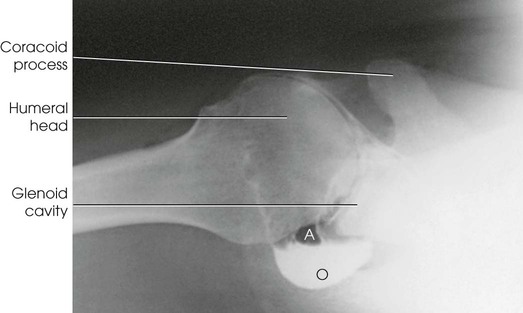

Arthrography (Greek arthron, meaning “joint”) is radiography of a joint or joints. Pneumoarthrography, opaque arthrography, and double-contrast arthrography are terms used to denote radiologic examinations of the soft tissue structures of joints (menisci, ligaments, articular cartilage, bursae) after injection of one or two contrast agents into the capsular space. A gaseous medium is used in pneumoarthrography, a water-soluble iodinated medium is used in opaque arthrography (Fig. 12-2), and a combination of gaseous and water-soluble iodinated media is used in double-contrast arthrography. Although contrast studies may be made on any encapsulated joint, the shoulder is the most frequent site of investigation. The joints discussed in this chapter—shoulder, knee, and hip—are the ones most likely to be imaged using radiographic contrast arthrography. Other joints may be imaged occasionally with arthrography. As noted previously, MRI, CT, and US are the modalities most likely to be used to demonstrate pathologies of the joints and associated soft tissues.

Arthrography of the shoulder is performed primarily for the evaluation of partial or complete tears in the rotator cuff or glenoid labrum, persistent pain or weakness, and frozen shoulder. A single-contrast technique (Fig. 12-4) or a double-contrast technique (Fig. 12-5) may be used.

The projections most often used are the AP (internal and external rotation), 30-degree AP oblique, axillary (Figs. 12-7 and 12-8), and tangential. (See Volume 1, Chapter 5, for a description of patient and part positioning.)